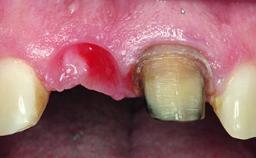

Replacement of an Upper Right Central Incisor with Root Resorption: Ridge Preservation, Delayed Placement of an NC Bone Level Roxolid Implant

A 32-year-old female Caucasian patient with a compromised maxillary right central incisor was referred to us by a general dentist. Her chief complaints were discomfort and mobility of tooth 11 with unsatisfactory esthetics due to discoloration. The patient reported a previous trauma, some years earlier, as the origin of pathology on the afflicted tooth. Anamnesis was negative for any other dental or periodontal pathology in the remaining dentition. The patient did not take any medication and reported to be a light smoker (5–10 cigs/day). She had high esthetic expectations of her treatment. The extraoral examination revealed a high smile line with full exposure of her maxillary teeth and surrounding soft tissue in the area between the second premolars.

Soft Tissue Anatomy Intact Defective

Soft Tissue Contour and Volume Slightly compromised